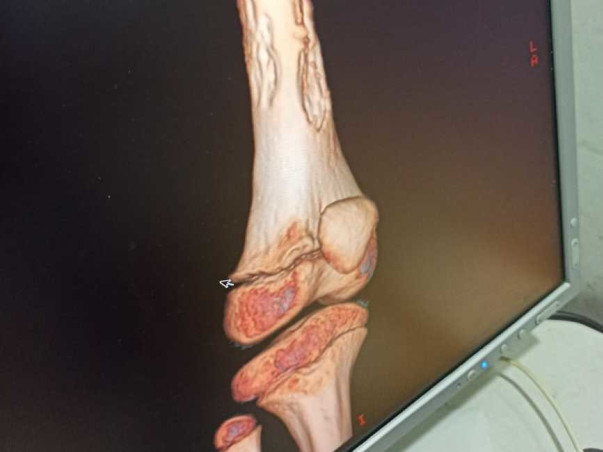

This Girl named Deekshitha M C aged 6 years is suffering from Bone cancer for one year, unfortunately, this little girl's family is not in a condition to fulfill the medical needs to cure her cancer, her father is working as a clerk in a small steel store.

The treatment would cost her more than 20 Lakhs. however, she is already gone through 2 cheemo Sessions, needs to undergo for further sessions.

attached are all the proofs with the estimated bill from the hospital